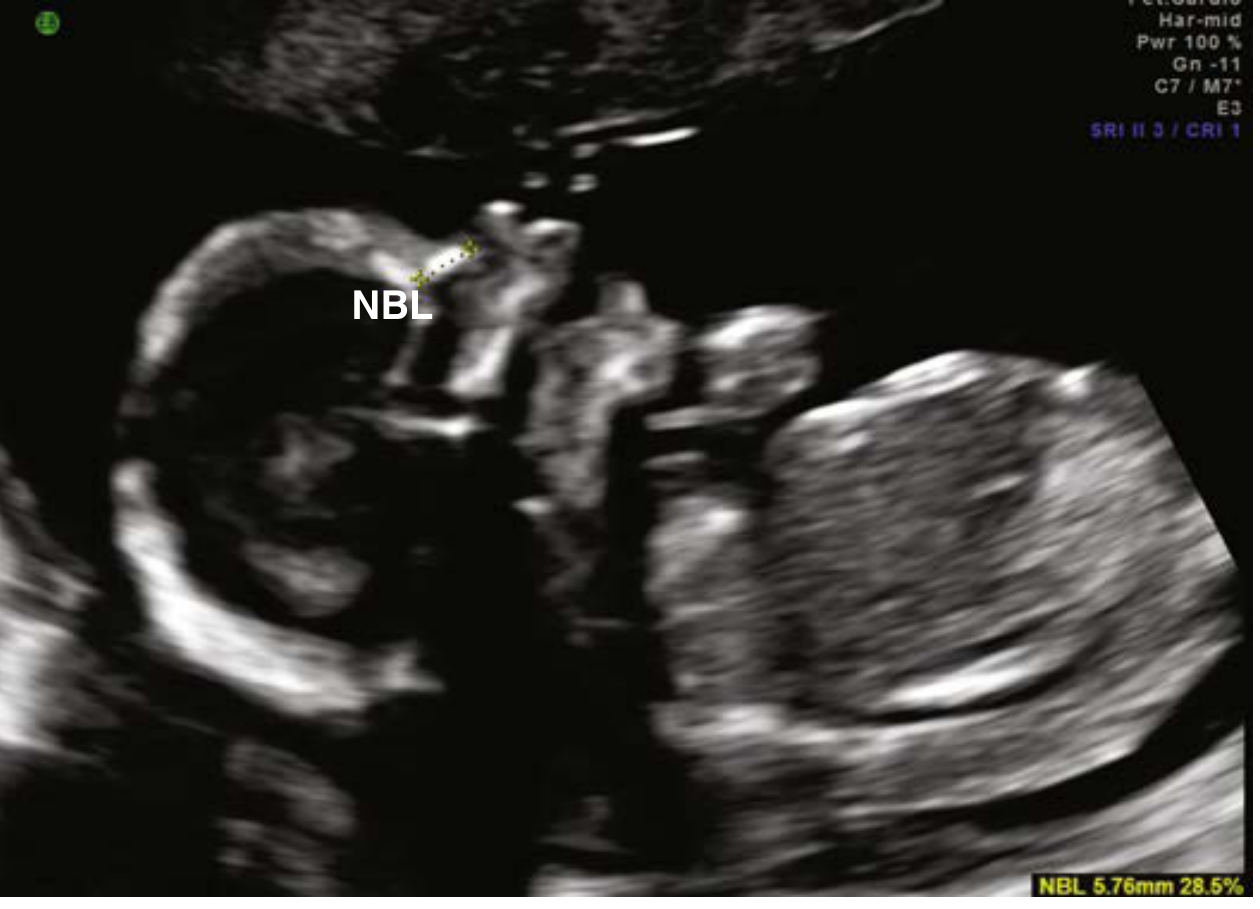

• Orbits, facial profile, nasal bone, upper lip

Fetal nasal bone

Figure: Fetal profile with nasal bone (marker for Down syndrome screening)

Absent nasal boneTrisomy 21